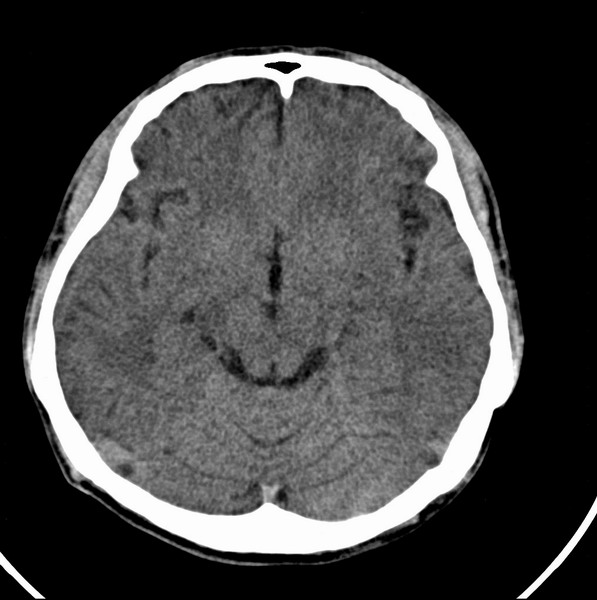

男、29

突发痴呆,失语,记忆减退,反应迟钝二十小时。

右侧额叶低密度影,边界清晰,无占位效应,符合:额叶皮质脑软化灶。

双额叶脑沟增深增宽,皮质性脑萎缩可以考虑么?

考虑右侧额叶脑软化灶;建议必要时行mri检查排除其他。